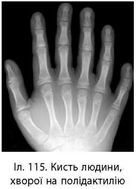

Генні хвороби - спадкові хвороби, спричинені генними мутаціями. Ці хвороби можуть бути домінантними аутосомними (полідактилія) (іл. 115) або рецесивними аутосомними (фенілкетонурія, хвороба Тея-Сакса), рецесивними зчепленими з Х-хромосомою (гемофілія, дальтонізм), зчепленими з Y-хромосомою (іхті

оз). Плейотропною дією одного гена пояснюється хвороба Марфана.